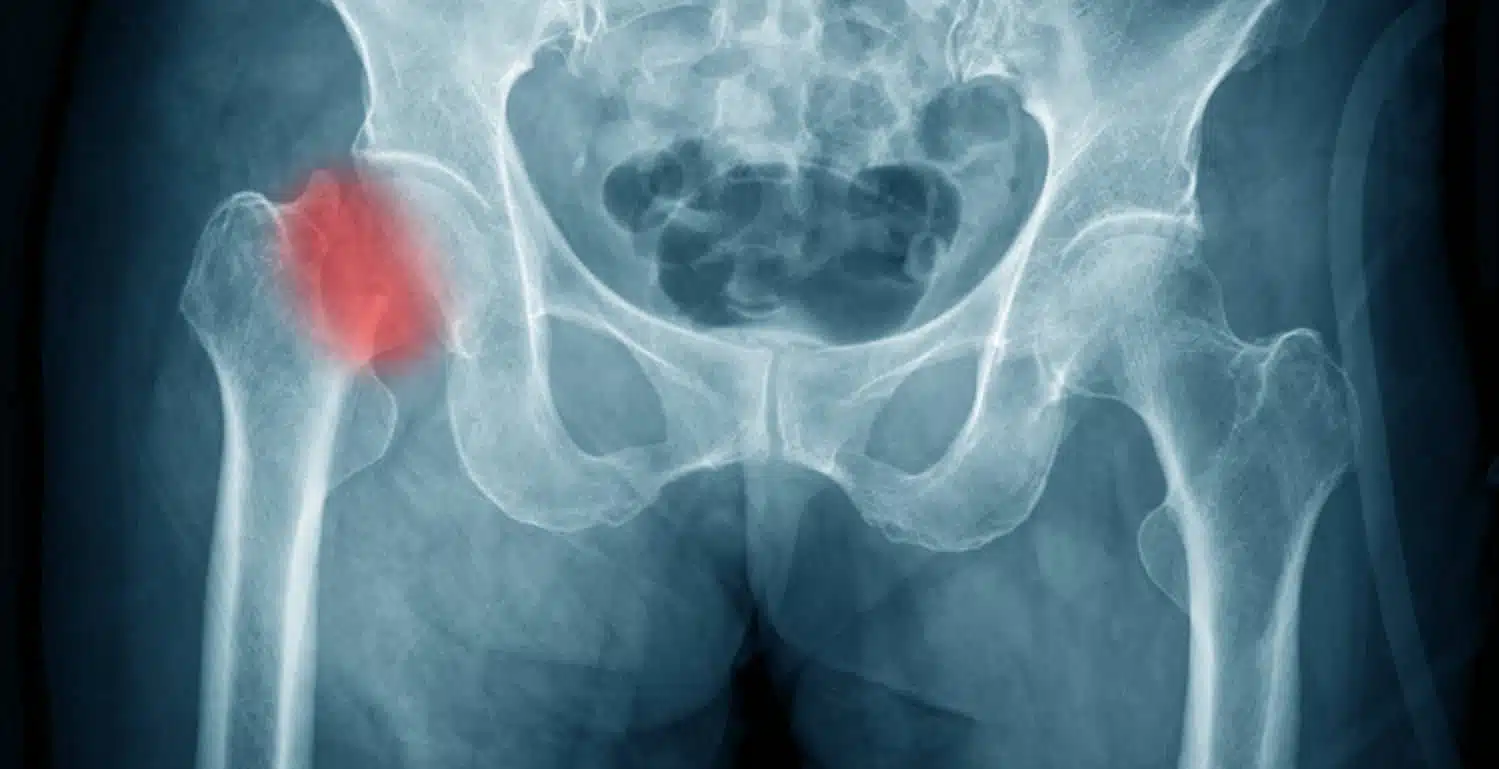

يتم تشخيص الكسر عادة باستخدام تصوير الأشعة السينية للحوض لتحديد تفاصيل الكسر بدقة، يطلب من الطبيب إجراء فحص بالأشعة المقطعية، حيث يجري الدكتور عمرو أمل أفضل دكتور عظام في مصر تقييم شامل للأعضاء الداخلية والأوعية الدموية والأعصاب المحيطة للتأكد من عدم وجود إصابات إضافية مرتبطة بالكسر.

علاج شرخ مفصل الحوض يتم تحديده وفقاً لمدى شدة الإصابة التي قد تعرض لها الفرد وعمره، حيث يقوم الطبيب المتخصص في البداية بتشخيص الحالة جيداً من خلال طلب صور إشاعات واضحة تبين العظام بطريقة واضحة مدى الضرر الواقع عليها، وبعد ذلك يبدأ في تطبيق العلاج المناسب للمريض وينصحه بالراحة طوال فترة العلاج وتجنب القيام بأي حركة خاطئة مع اتباع برنامج علاج طبيعي يسرع من عملية الشفاء.